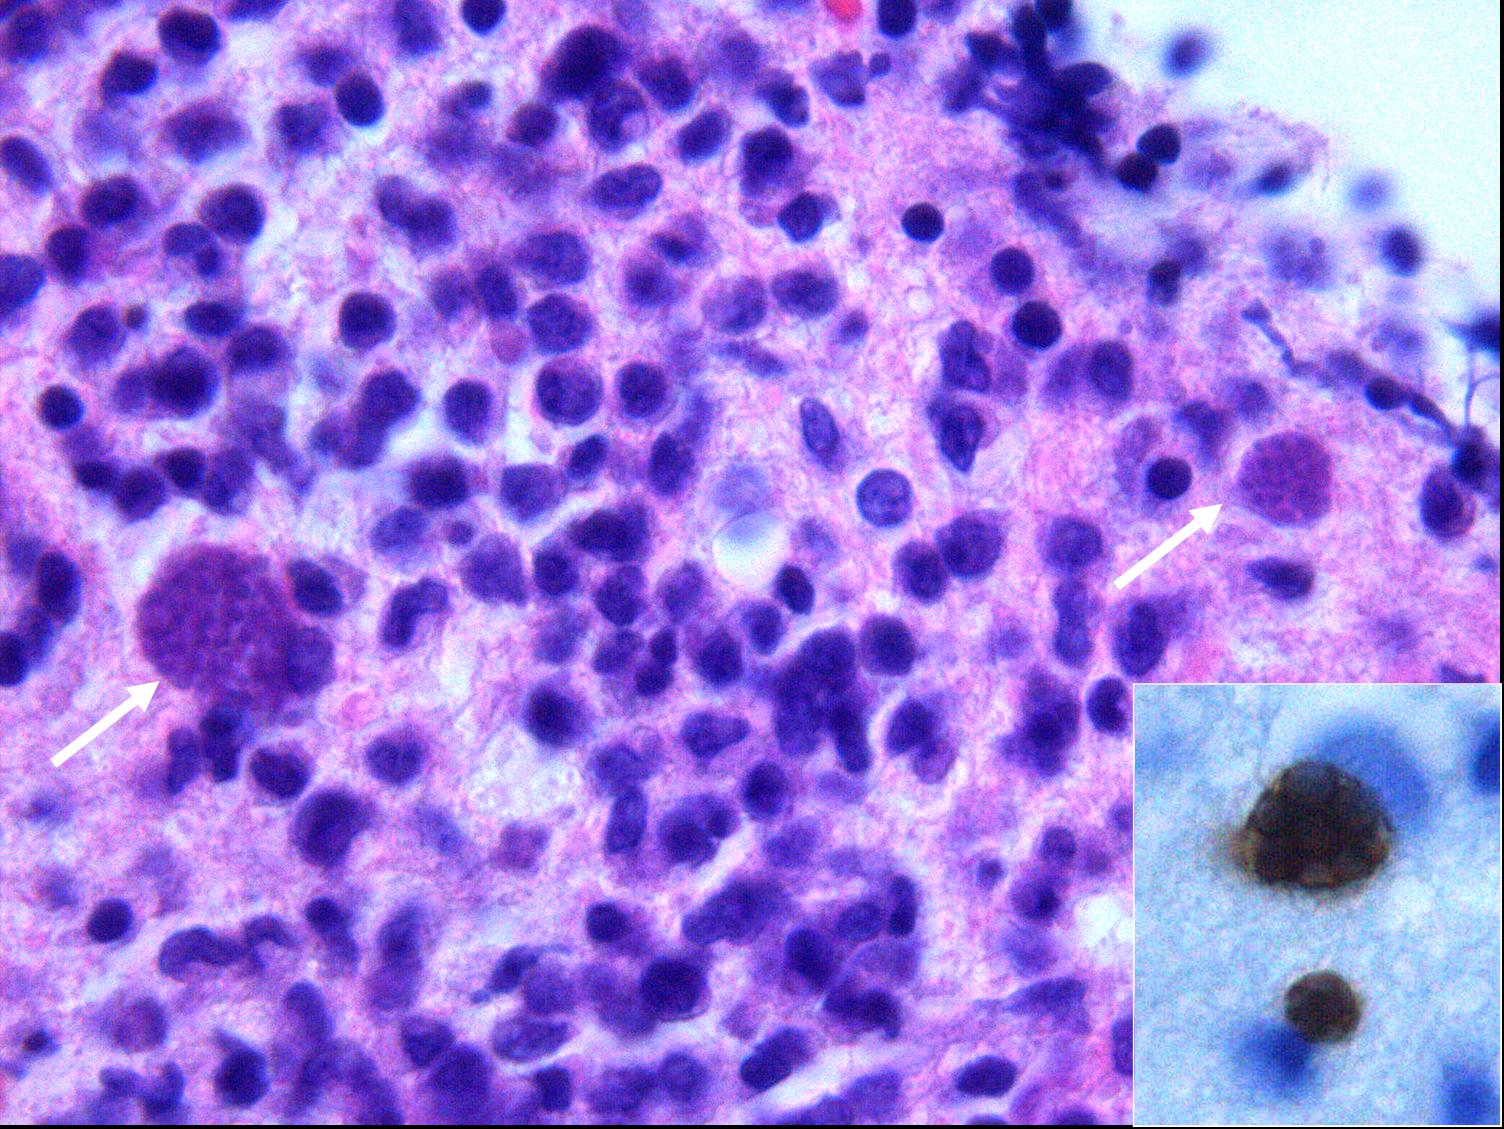

Grundsätzlich natürlich klar - warum sollte es im Hirn weniger Parasiten oder Bakterien geben als in der Haut oder im Darm? Aber das Wirken der Hirnparasiten ist, auch dem SZ-Artikel zufolge, bei weitem noch nicht so gut verstanden wie das der Darmflora, so daß vieles wohl doch eher Spekulation ist. (Gibt es eigentlich neuere Arbeiten zu dem Thema?) i-41c780a91500e31b84eaf22c4ee7f182-Toxoplasmose.jpg de.wikipedia.org/w/index.php?title=Datei:Toxoplasmose.jpg&filetimestamp=20081213004344 Bleibt die Frage, ob Topologen und Differentialgeometer von unterschiedlichen Parasiten befallen sind? Und welche Würmer man Kindern geben muß, damit sie in der Klassenarbeit die Geometrie-Beweise schaffen?